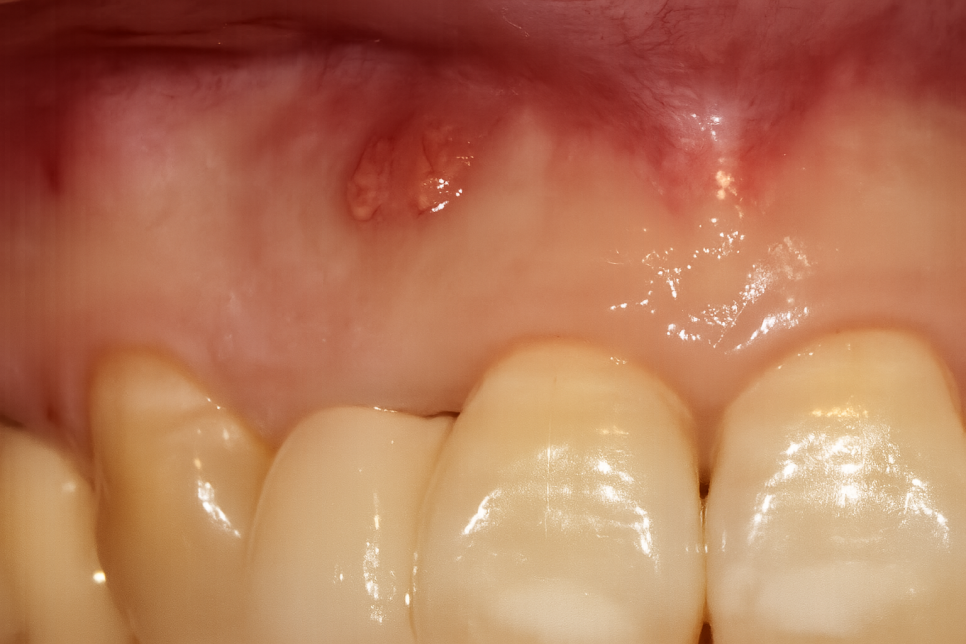

사진을 보시면 잇몸에 볼록하게 여드름이

올라온 것을 알 수 있습니다.

대개 이러한 양상을 보이는 이유는

치아 뿌리에 커다란 염증이 생겨나

심화되면서 볼록한 여드름이

잇몸에 올라오는 것이랍니다.

눈으로 보는 것만으로는 정확하게

문제를 파악하기 어렵기 때문에

방사선사진을 찍어 내부가 어떤 상태인지

체크해 보는 과정을 거칩니다.